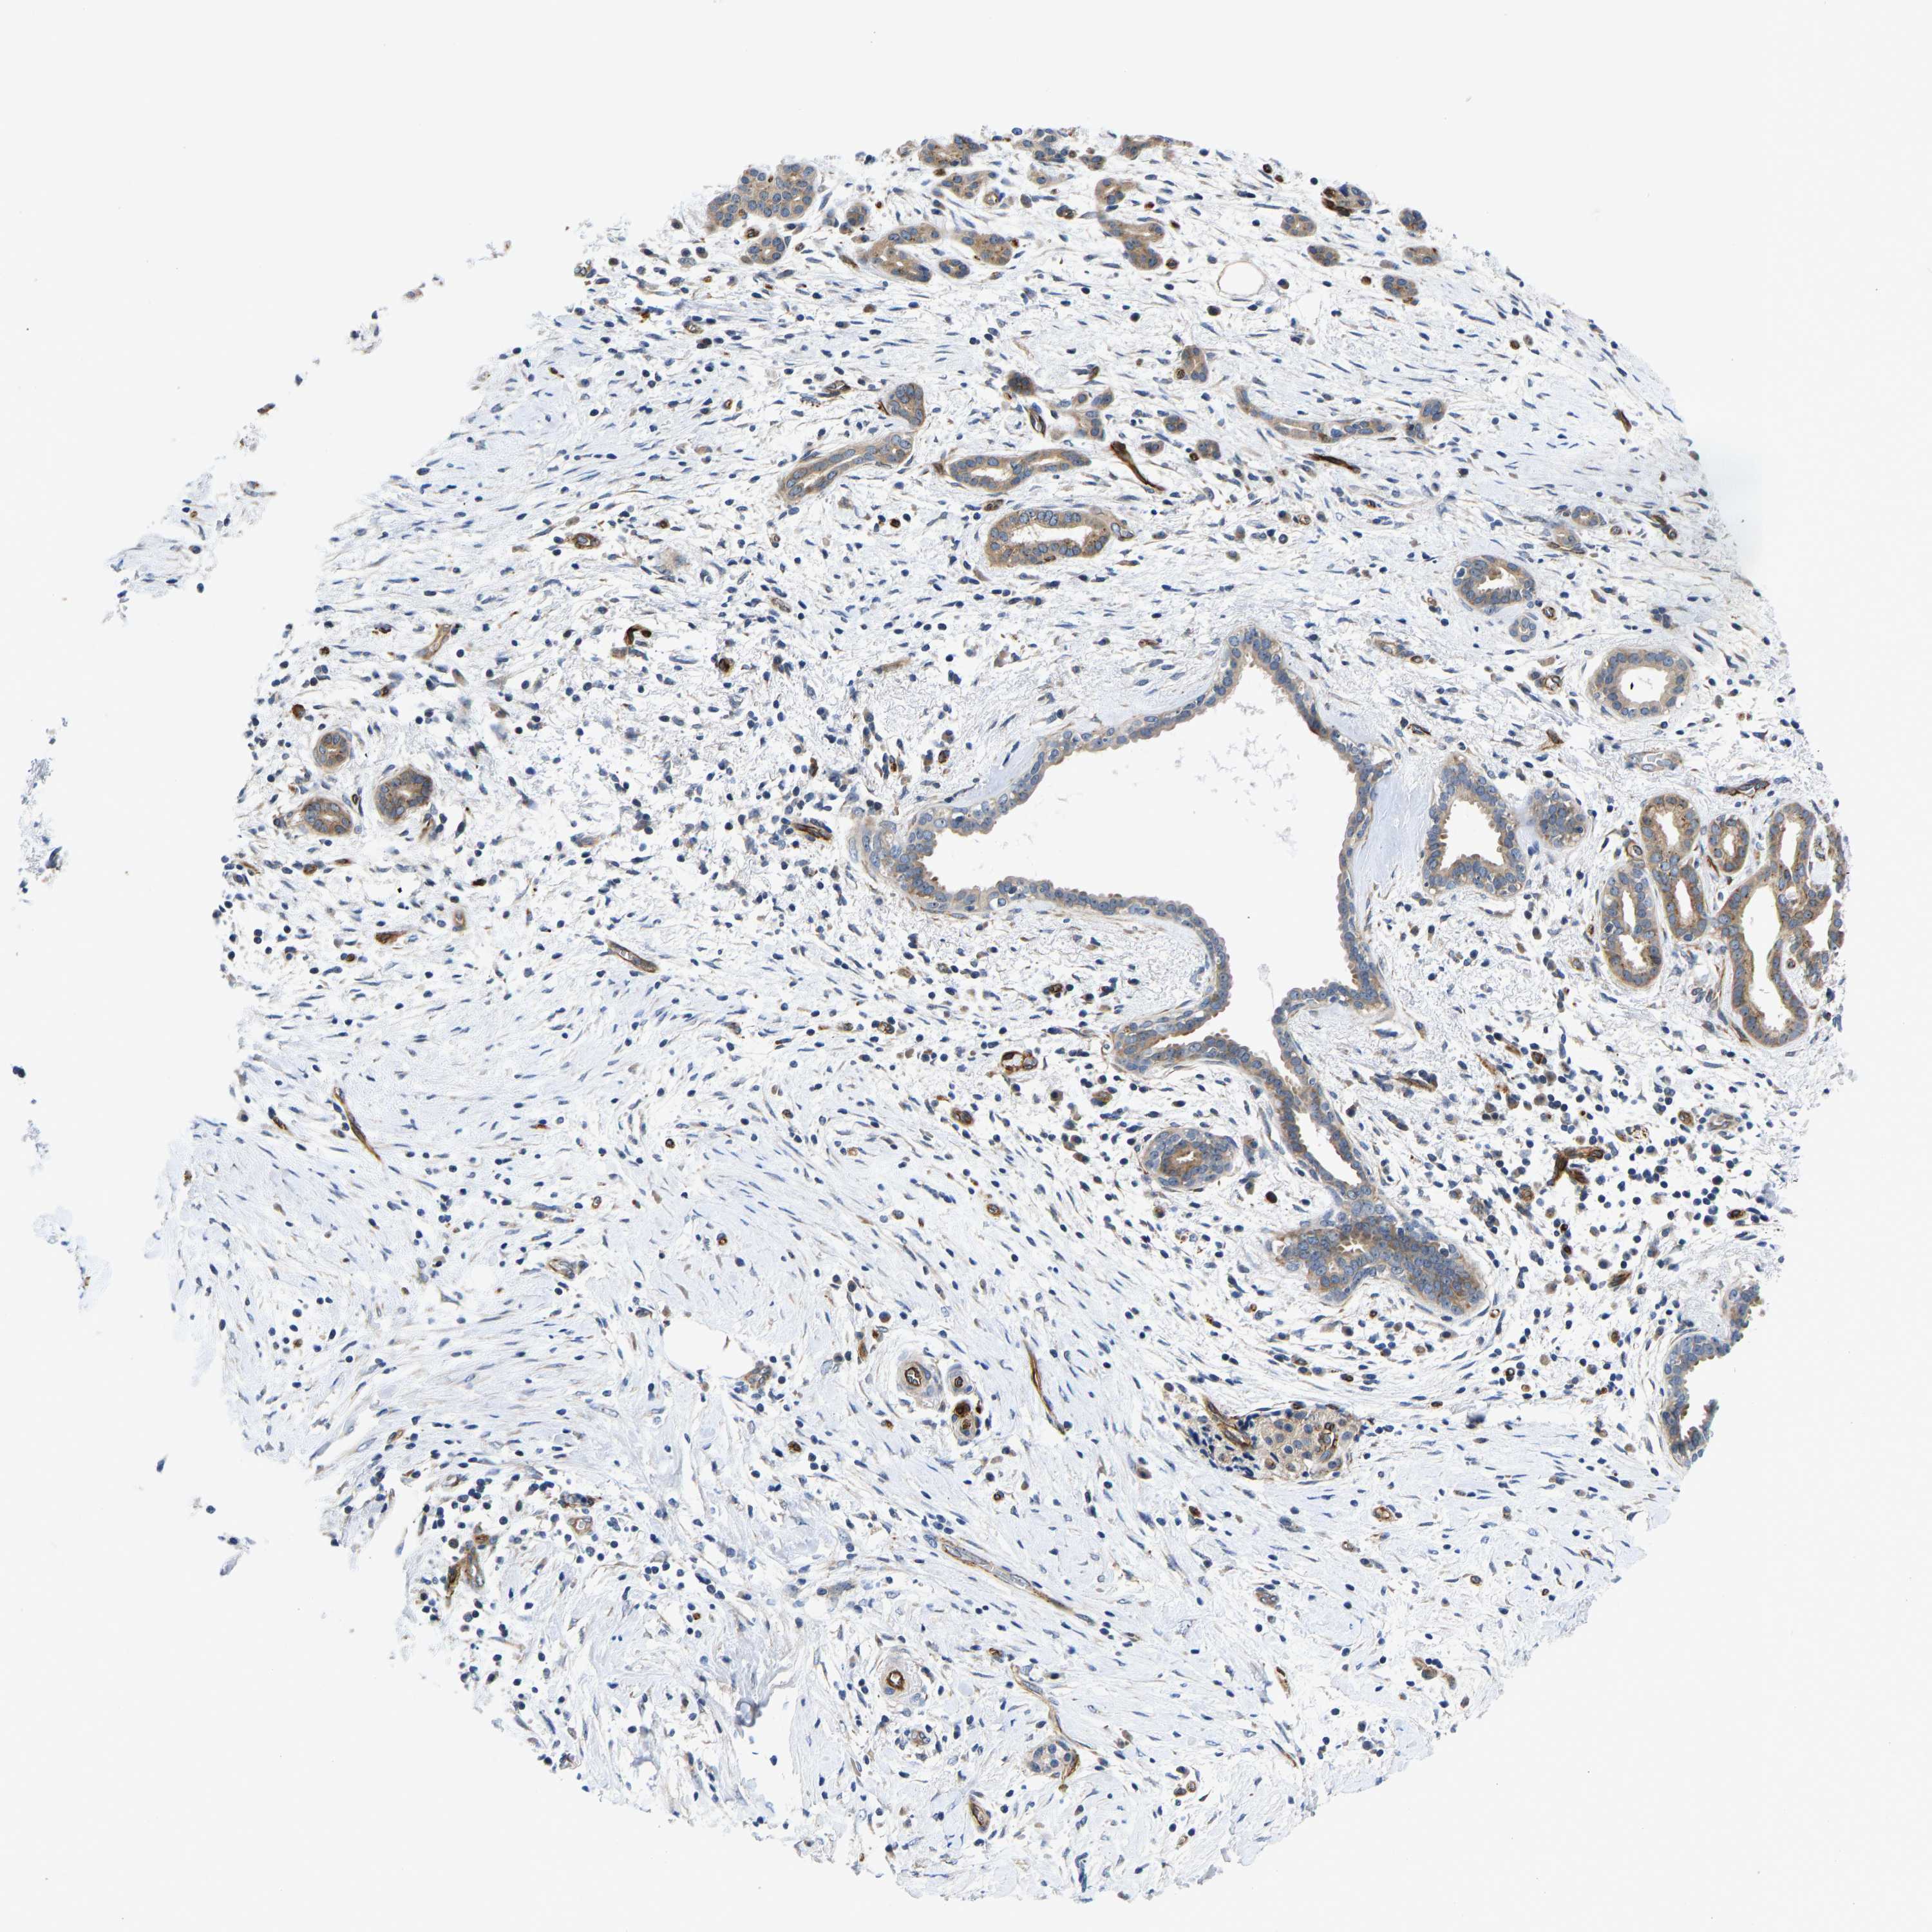

PANCREATIC CANCER - Protein expressioni

A mouse-over function shows sample information and annotation data. Click on an image to view it in a full screen mode. Samples can be filtered based on level of antibody staining by selecting one or several of the following categories: high, medium, low and not detected. The assay and annotation is described here.

Note that samples used for immunohistochemistry by the Human Protein Atlas do not correspond to samples in the TCGA dataset.

Antibody stainingi

Antibody staining in the annotated cell types in the current human tissue is reported as not detected, low, medium, or high, based on conventional immunohistochemistry profiling in selected tissues. This score is based on the combination of the staining intensity and fraction of stained cells.

Each image is clickable and will lead to virtual microscopy that enables deeper exploration of all samples and also displays staining intensity scores, fraction scores and subcellular localization as well as patient and tissue information for each sample.

Antibody HPA013816

Antibody HPA015622

Adenocarcinoma, NOS